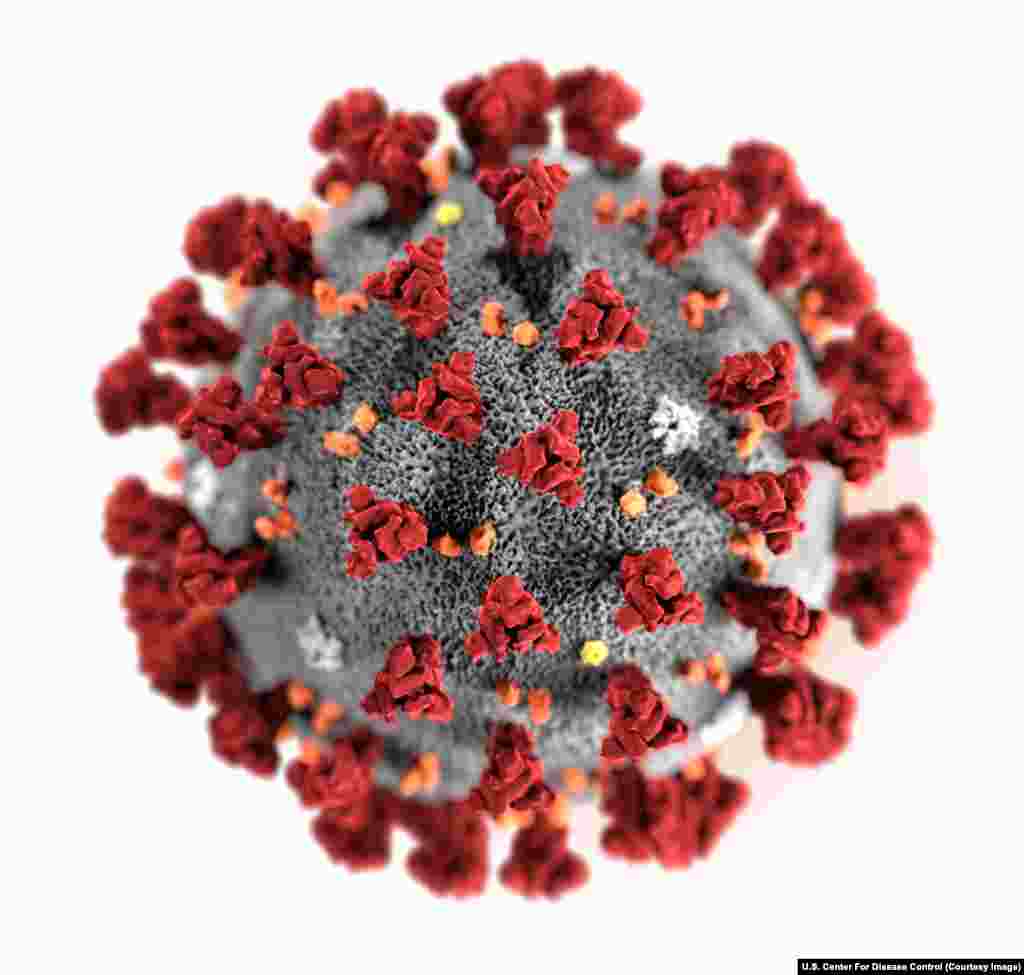

5

Компьютерная анимация нового коронавируса, вызывающего заболевание COVID-19.

Поверхность вируса усеяна шиповидными отростками.

Поверхность вируса усеяна шиповидными отростками.